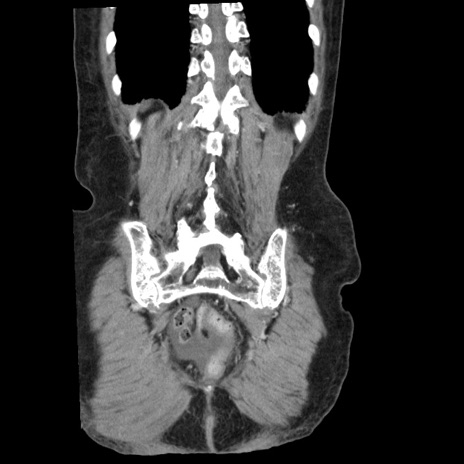

症例1(冠状断像)

横断像